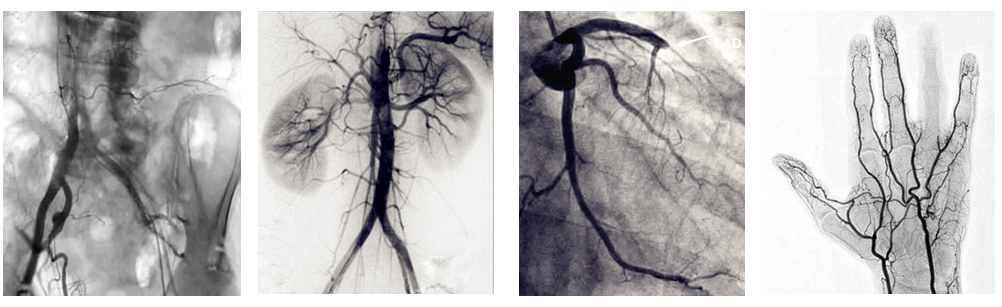

介入c臂機可以把不需要的組織影像刪除掉,只保留血管影像。圖像清晰,分辨率高,對觀察血管病變,血管狹窄的定位測量,診斷及介入治療提供了真實的立體圖像,還具有多種工作模式,靈活方便,滿足各種臨床需要,為各種介入治療提供了必備條件。

介入c臂機臨床圖片